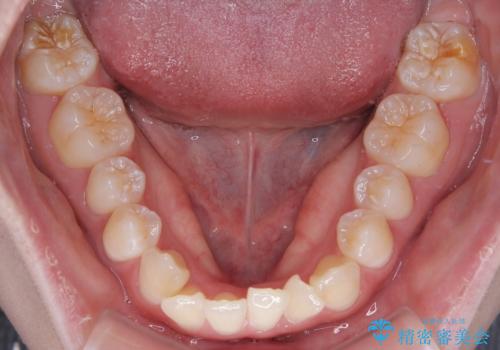

- 「前歯のデコボコ(叢生)をきれいに整えたい」とのことでご来院されました。

マウスピース矯正も検討されていましたが、「装着時間の自己管理が難しそう」「なるべく早く治療を終えたい」とのご希望から、ワイヤー矯正を選択されました。

目立ちにくさと費用のバランスを考慮し、プラスチックブラケット+メタルワイヤーを採用。日常生活でも装置の存在感を気にせずお過ごしいただけます。

患者様の協力もあり、およそ1年間で治療を完了。スムーズな歯の移動を実現しました。

上下の正中(真ん中のライン)もずれることなく、バランスの取れた美しい歯並びに。笑顔に自信を持てる仕上がりとなりました。